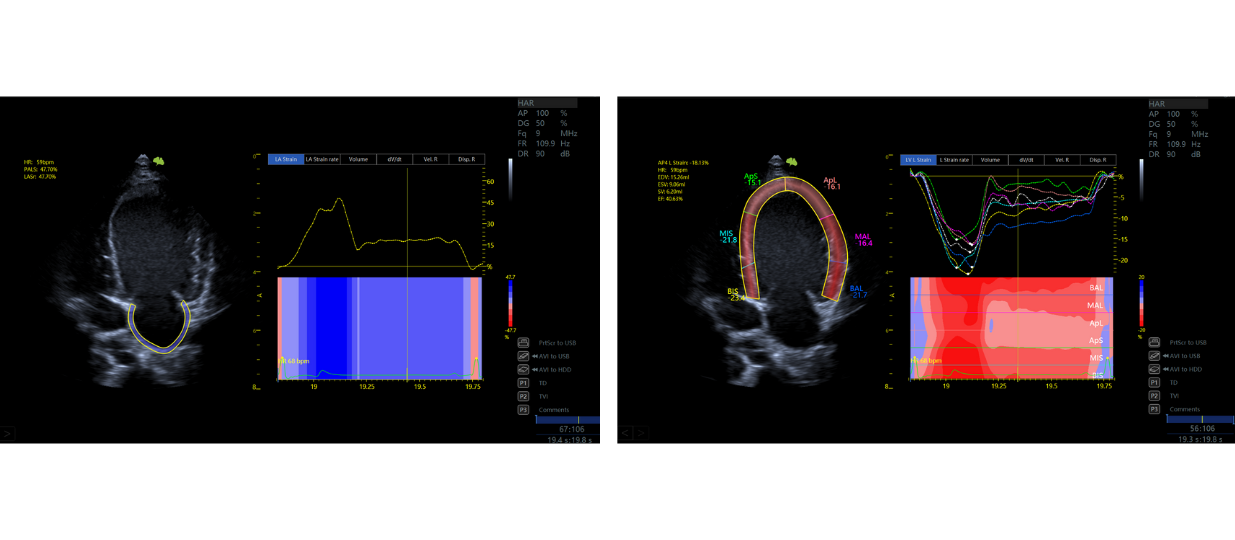

The Ultimus 9V is equipped with VINNO's revolutionary Multi-modal Ultrafast Sonography Enhanced (MUSE) platform, with the unique Tri-modal Imaging Acquisition (TIA).

Its flexibility and powerful processing allow the system intelligently apply the most appropriate imaging acquisition mode from 3 modalities to reconstruct the best imaging presentation:

Compared to traditional platforms, the MUSE platform enables higher frame rates and greater clarity, relying on a complete acoustic data processing system to dramatically increase penetration and resolution.